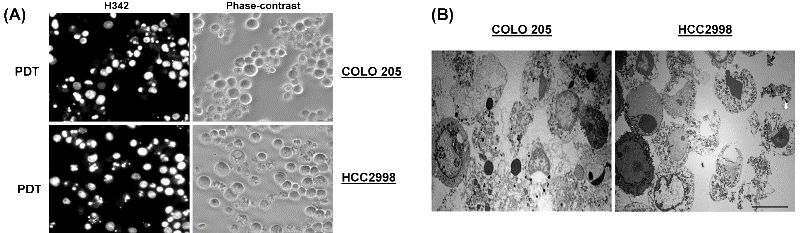

Figure 2: HAL-PDT-induced apoptosis of the COLO 205 and HCC2998 cells. (A) Fluorescence and corresponding phase-contrast images of the apoptotic COLO 205 and HCC2998 cells at 20 h after HAL-PDT. (B) Electron microscopic images of the apoptotic COLO 205 and HCC2998 cells at 20 h after HAL-PDT (Bars: 10 μm).